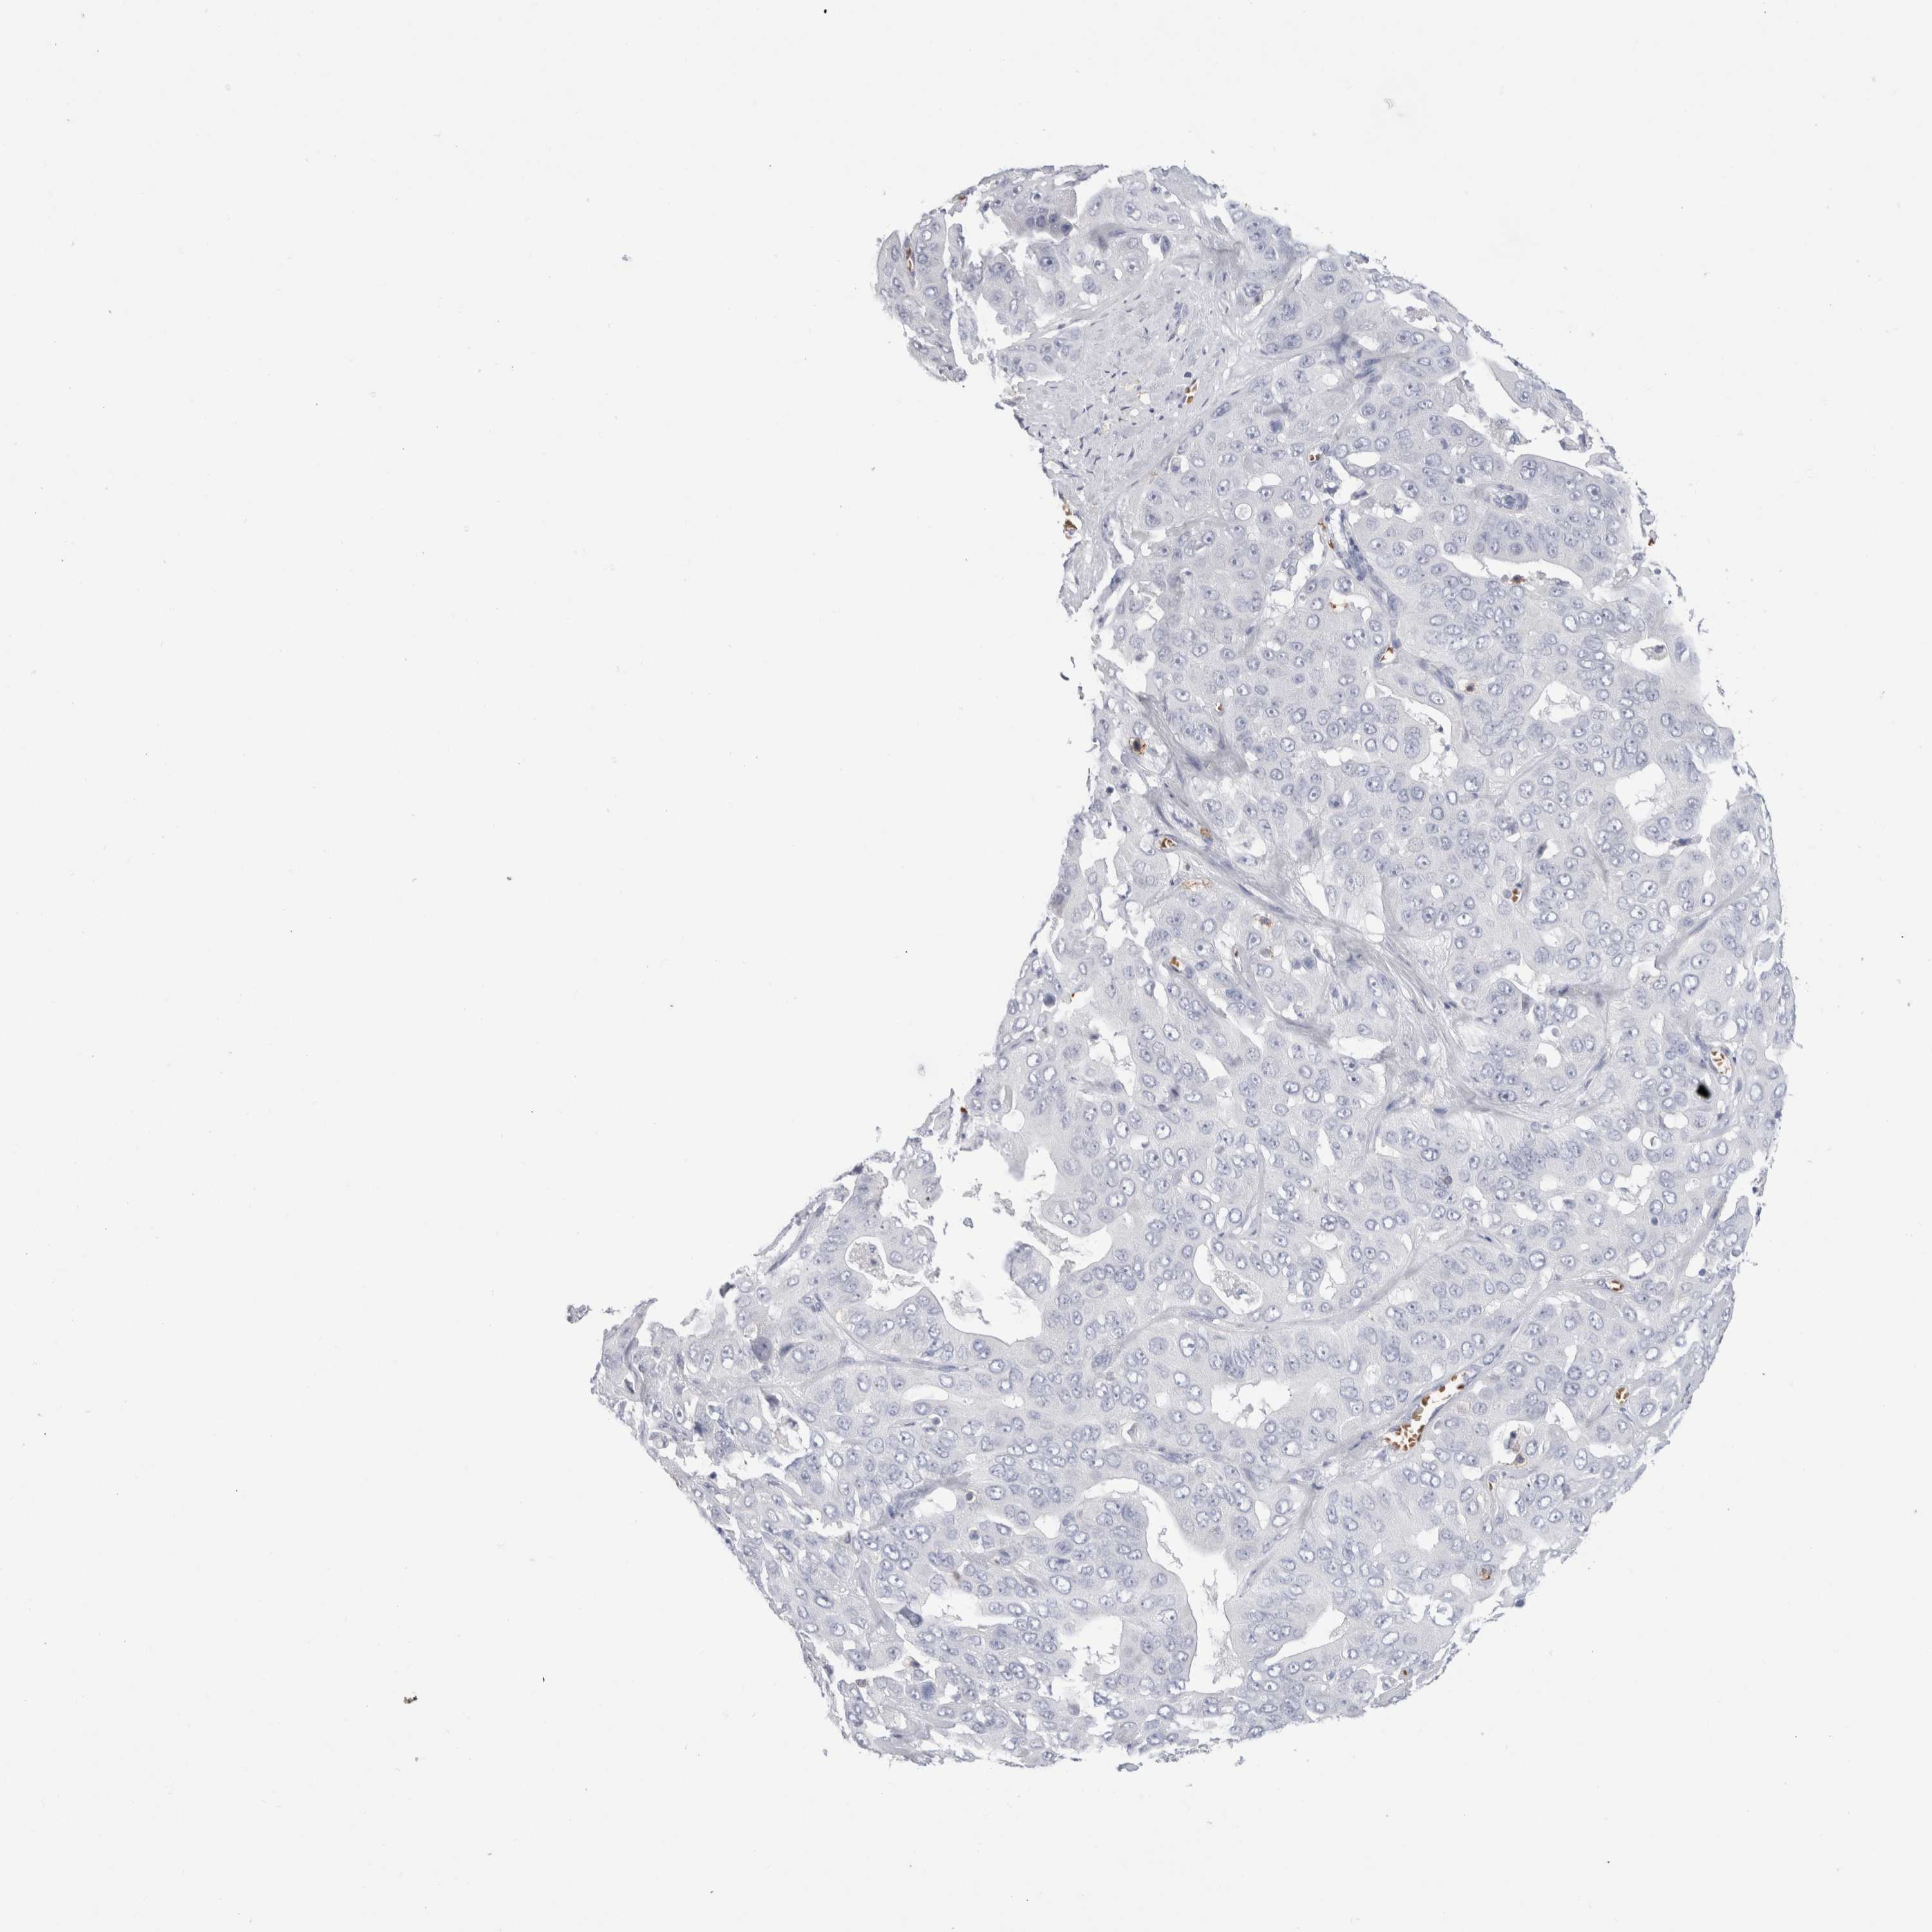

LIVER CANCER - Protein expressioni

A mouse-over function shows sample information and annotation data. Click on an image to view it in a full screen mode. Samples can be filtered based on level of antibody staining by selecting one or several of the following categories: high, medium, low and not detected. The assay and annotation is described here.

Note that samples used for immunohistochemistry by the Human Protein Atlas do not correspond to samples in the TCGA dataset.

Antibody stainingi

Antibody staining in the annotated cell types in the current human tissue is reported as not detected, low, medium, or high, based on conventional immunohistochemistry profiling in selected tissues. This score is based on the combination of the staining intensity and fraction of stained cells.

Each image is clickable and will lead to virtual microscopy that enables deeper exploration of all samples and also displays staining intensity scores, fraction scores and subcellular localization as well as patient and tissue information for each sample.

Antibody HPA022132

Antibody HPA052381

Antibody CAB002493

Antibody CAB025255

Cholangiocarcinoma

Carcinoma, Hepatocellular, NOS